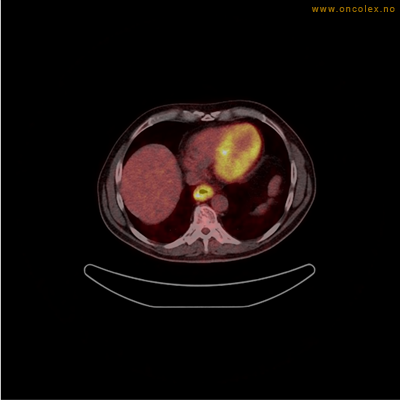

Vev som tar opp mer radioaktivt stoff, synes som hvite områder som lyser opp mer i forhold til annet vev som tar opp mindre sukker.

Adenokarsinom distalt i spiserør. Fysiologisk opptak i hjertemuskulatur.

Adenokarsinom langt nede i spiserøret.

Spredningssvulster til lever med sentral nekrose.